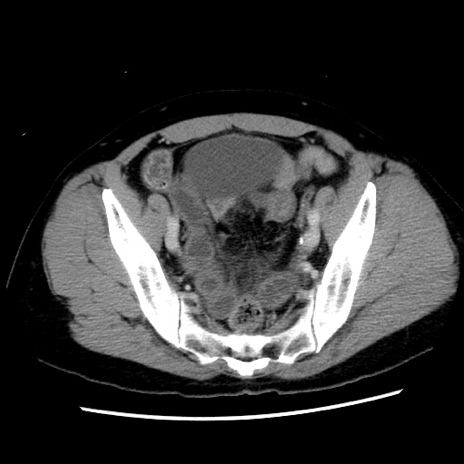

症例10(横断像)

【症例】 50歳代女性

【主訴】 腹痛

【現病歴】前日生レバーを食べた。今朝に排便あり。 昼前に突然発症の腹痛を生じ、当院救急外来を受診した。

【既往歴】 子宮筋腫にてで子宮全摘後

【身体所見】 意識清明、腹部:平坦、軟、下腹部やや左を中心に圧痛・反跳痛あり、筋性防御あり

【データ】WBC 7800、CRP 0.07